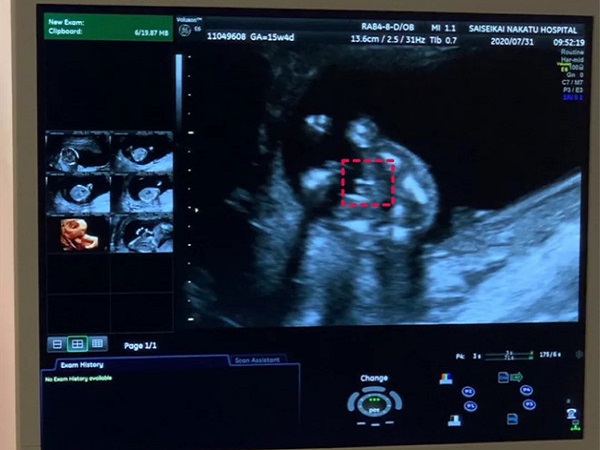

网上流传通过怀孕13周的Nt单子可以看出胎儿性别,但是很多孕妈妈都不知道具体应该怎么看。下面为大家整理了13周已生男宝的nt单子,大家可以对照看一下。

其实在怀孕13周的时候,胎儿的生殖器官已经基本发育完全,通过B超检查是能够看到的,但是由于国家禁止,因此医生是不会告知父母胎儿性别的。据此,网上就有不少人传通过Nt单子上的图片也是可以看到胎儿的生殖器官特点的。

胎儿两腿间有亮点就说明是男宝宝

认为如果nt单子上胎儿两腿之间有白色的亮点,那就是男孩子的睾丸,所以出现白点的nt单子大概率就是男宝宝。但是如果看到胎儿两腿之间是三条白线的话,其实就是女孩子***的形状,怀女宝宝的概率会更大一些。并且有已经生育男宝宝的姐妹验证,nt单子上确实有白点存在。

但其实,nt单子的图像还会受到宝宝姿势和医生检查位置的影响,因此单纯通过nt单子有无亮点和白线来判断生男生女还是不可靠的。建议大家不要太关注宝宝的性别,应该多关注孩子的健康状况。